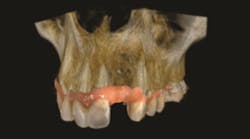

3. Then, using interactive software for treatment support, the data from the CBCT scan and digital impression are merged together. Figures 1-3.

What is the point of obtaining both extraoral and intraoral images? While the clinician can gain valuable insight about the mandible or maxilla, CBCT does not provide enough information about the surface detail of the teeth or soft tissues.2 When CBCT information is combined with the digital impression in the interactive treatment software, the doctor’s diagnostic capabilities are greatly enhanced, and, consequently, so is treatment planning.